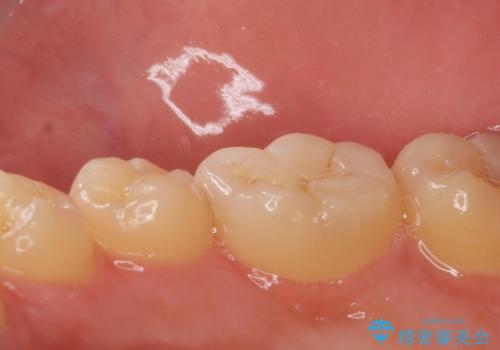

歯と歯の間に虫歯(コンタクトカリエス)がありましたので、拡大鏡下で虫歯を取り、白い詰め物(e-maxインレー)で治療を行いました。